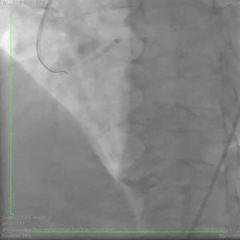

Imagem da semana

Se alguns têm um TCE, com certeza esse aí é o PAPAI dos TCEs rs.

Uma belíssima origem anômala da coronária direita do tronco da coronária esquerda, vista ao cateterismo cardíaco.

E um Feliz Dia dos Pais para todos os papais Dozers!